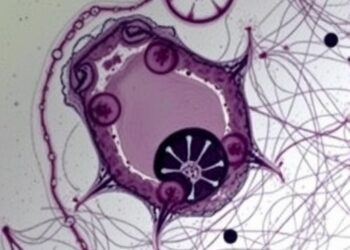

Chimeric Antigen Receptor (CAR)–Engineered Cells:

- CAR-T, CAR-NK, and CAR-macrophages are engineered to specifically recognize AML antigens to kill leukemia cells.

- Activated T cells release cytokines (e.g., IFN-γ) to promote further immune activation.

- Present AML-associated antigens using dendritic cells (DCs) to activate T cells and induce cytotoxic T lymphocytes.